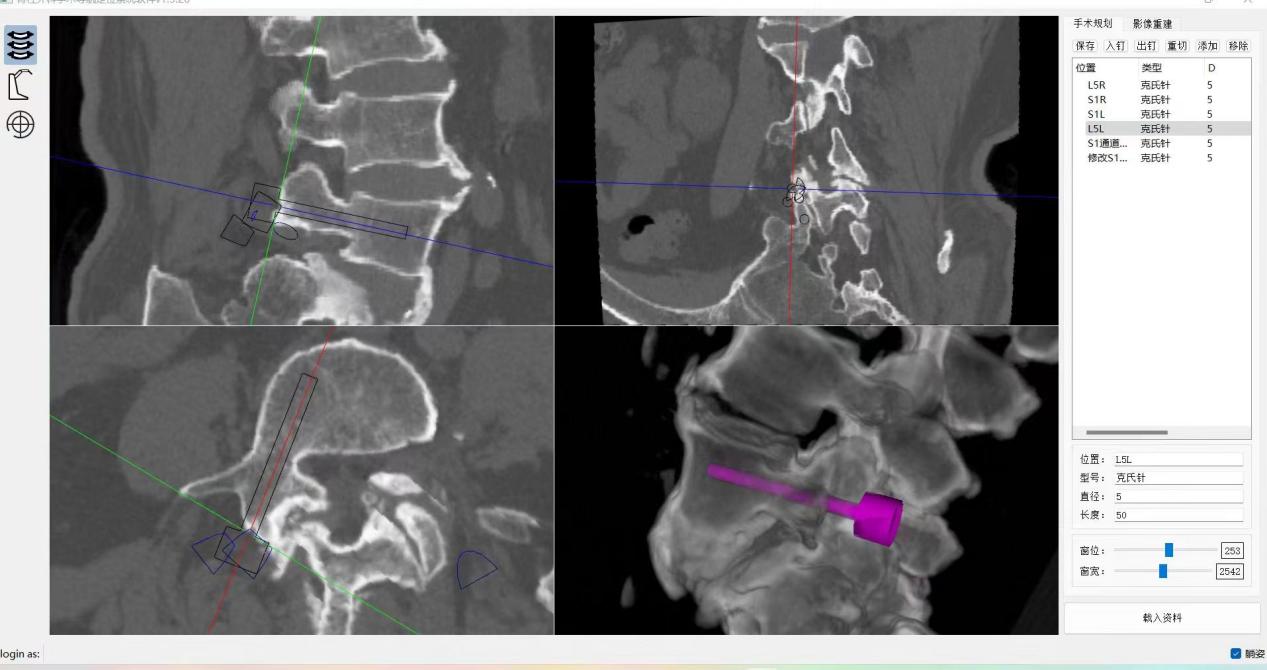

患者64岁,因间断性腰痛30年,加重伴间隙性跛行2年,辗转北京及西安多所医院,均建议采取传统外科开放手术治疗,患者因担心手术风险,迟迟不愿手术。经多方打听,患者慕名找到李全义主任医师。入院后李全义主任医师仔细研究患者的疾病特点,经过充分的沟通,决定采用目前骨科先进的微创、精准技术—机器人辅助微创手术。李全义主任医师团队顺利为患者实施ORTHBOT脊柱机器人辅助镜下腰5椎体滑脱复位椎管减压椎间融合内固定术,以机器人辅助微创手术解决了患者的痛苦,减少手术创伤及并发症,缩短手术时间。手术利用术前患者的影像学资料,模拟建立穿刺路径及各项参数,极大地优化手术方案使其更加精准、安全、有效,显著降低了制钉过程中神经根损伤的风险。

ORTHBOT脊柱机器人术前设计及术中穿刺